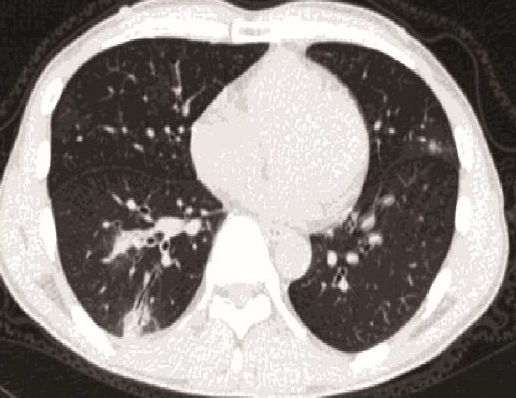

A wide variety of typical and atypical CT abnormalities have been reported for COVID-19 patients in various studies [58, 59]. So, we tested our models on external CT images extracted from these two publications as they feature typical findings of COVID-19 pneumonia marked by specialists. In order to make sure that not any of the extracted images are unintentionally included in our datasets, specifically the COVID19-CT dataset, we use the model trained on the SARS-CoV-2 dataset. First, the InceptionV3 model is employed to classify the extracted CT images. The model is able to correctly classify the given CT images as COVID-19. Second, in order to interpret the model’s generalization capabilities, we apply the Grad-CAM technique to visualize the regions of abnormalities that are considered. By assessing the different CT images in Figure 15, we can see that the model accurately localizes the disease-related regions. Even more interesting is the fact that the model ignores any specific marks in the images like letters and only localizes the COVID-19 related regions. These visual explanations show the success of our models to learn relevant, generic visual features related to COVID-19 and are capable to correctly classify CT images outside the datasets on which they are trained.

Figure 16 shows various CT scans where only one lung is visible. The CT scans are also extracted from the paper [58] and show different CT manifestations of COVID-19 pneumonia marked by red squares. The InceptionV3 model is capable to classify them correctly as COVID-19, although it is trained on CT scans where the entire lung is visible. Intriguingly, when applying Grad-CAM we can see that all regions of abnormalities are accurately localized. This also proves the potential of our model to detect COVID-19 abnormalities in CT images outside the dataset used for training.